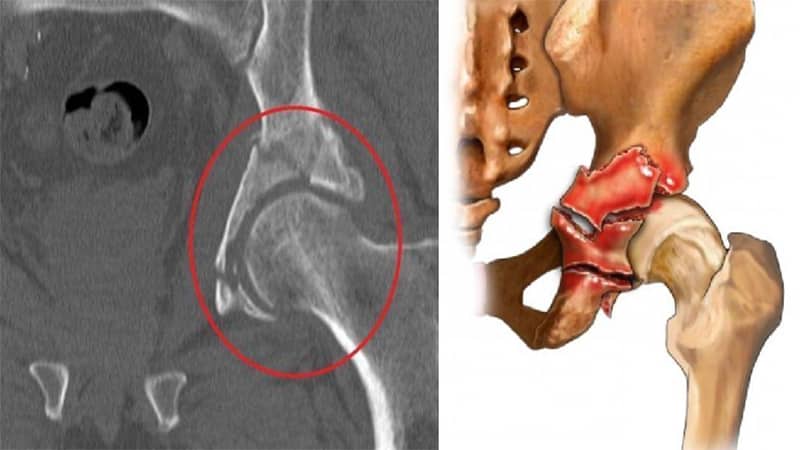

Перелом

Травмы тазовых костей часто возникают в результате дорожно-транспортных происшествий или падений. Переломы классифицируются на простые и сложные. Пострадавший испытывает интенсивную боль и не может двигать поврежденной ногой. Также могут наблюдаться укорочение конечности и ее аномальный поворот.

Для постановки диагноза используются рентгенография и компьютерная томография. На снимках четко видны место и тип перелома, а также наличие осколков.

Важно! Перелом вертлужной впадины требует срочной госпитализации. Первая помощь заключается в том, чтобы обеспечить пострадавшему горизонтальное положение и покой, дать обезболивающее средство и дождаться приезда скорой помощи.

Лечение таких травм включает в себя скелетное вытяжение и хирургическое вмешательство. Травмы вертлужной впадины могут привести к частичной или полной утрате подвижности, постоянной хромоте, укорочению конечности и развитию коксартроза.